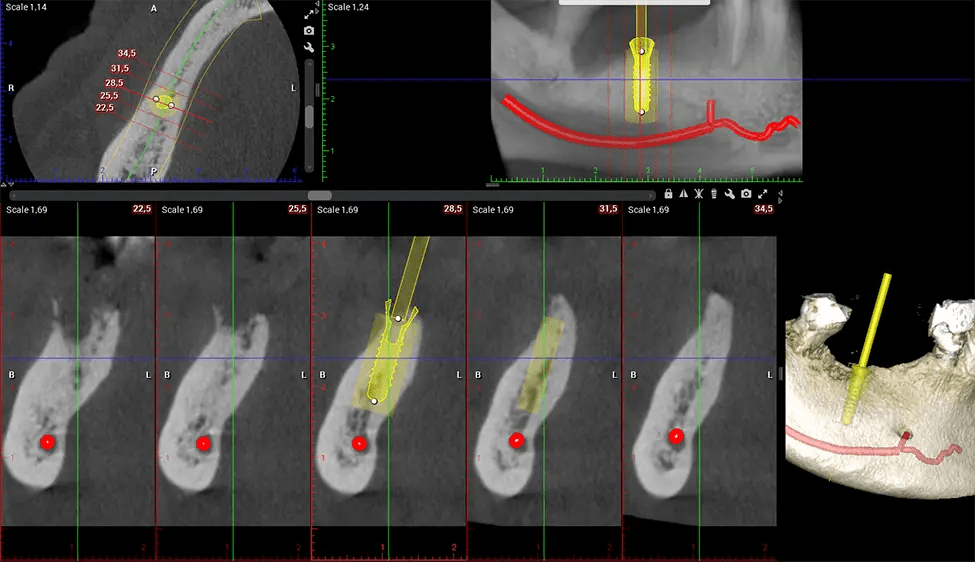

Tomografía computarizada de haz cónico (CBCT) es una técnica de imagen avanzada utilizada en odontología y cirugía maxilofacial para obtener imágenes 3D detalladas de las estructuras orales y maxilofaciales. Dr. G Estudio Dental, nuestro CBCT Los escáneres utilizan un haz de rayos X en forma de cono y un detector especializado para capturar imágenes desde diferentes ángulos. Posteriormente, una computadora combina estas imágenes para crear una representación tridimensional de la anatomía oral del paciente.

Esta exploración 3D, llamada tomografía computarizada de haz cónico, le brinda a su dentista una imagen más completa de su anatomía bucal y sus procesos patológicos que una radiografía tradicional. A diferencia de las radiografías convencionales, que capturan una imagen 2D de la boca desde varios ángulos, una exploración 3D toma varias radiografías digitales para una imagen. Proporciona una vista completa de la mandíbula, los dientes, los nervios y los tejidos blandos. Esta vista mejorada permite a los dentistas detectar problemas menores que no son visibles en las exploraciones 2D tradicionales, como muelas del juicio impactadas o fracturas óseas en la cavidad sinusal.

Después del proceso de escaneo, las imágenes de rayos X capturadas son procesadas por el CBCT software, que aplica algoritmos para reconstruir una imagen 3D detallada del área escaneada. El software compila estas imágenes de rayos X individuales y crea una representación digital 3D de la anatomía del paciente. La 3D reconstruida CBCT La imagen puede ser visualizada y analizada por el dentista o el radiólogo. Esta imagen puede manipularse, rotarse y ampliarse o reducirse para examinar estructuras específicas y evaluar el estado del paciente.